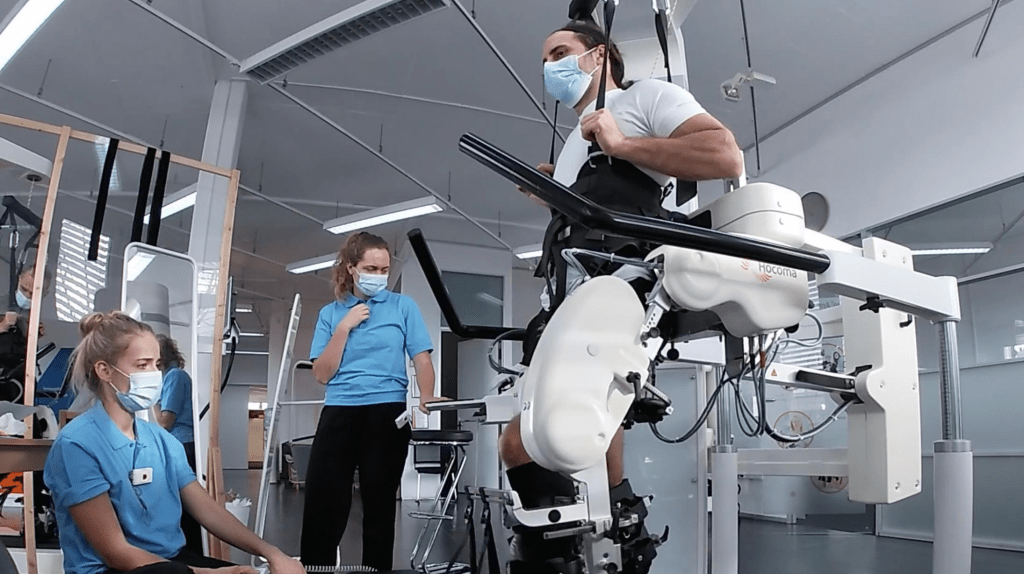

Revolutionary Neuroprosthetics for Spinal Injury Rehabilitation

Read more: Revolutionary Neuroprosthetics for Spinal Injury RehabilitationSource:Ecole Polytechnique Fédérale de Lausanne FULL STORY Spinal cord injuries are life-altering, often leaving individuals with severe mobility impairments. While rehabilitation robotics — devices that guide movement during therapy — have improved training for those with spinal cord injuries, their effectiveness remains limited. Without active muscle engagement, robotic-assisted movement alone does not sufficiently retrain the…